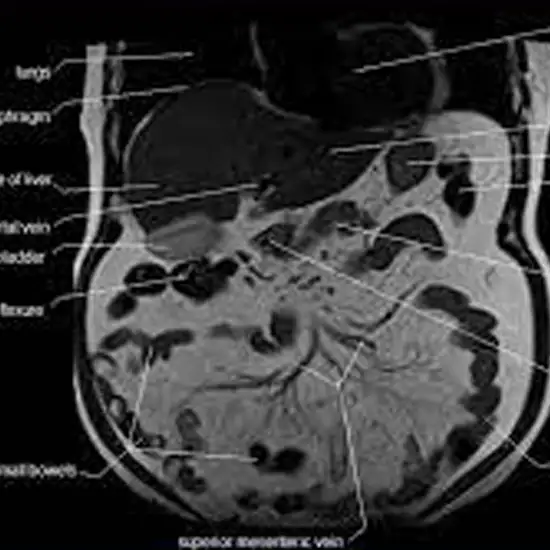

Umbilical Magnetic Resonance Imaging focuses on the umbilical masses' abnormalities and the areas around them.

Magnetic resonance imaging (MRI) is a painless procedure that creates pictures of the interior of the umbilical and its exterior. It produces cross-sectional imaging allowing surgeons to examine layers and organs without needing an operation.

MRI of the Umbilical Region is a Magnetic Resonance Imaging non-invasive medical diagnostic tool diagnostic tool used to diagnose the umbilical masses' abnormalities and the areas around them. MRI of the Umbilical Region is used to evaluate the disorder unspecific and cross-section imaging gets the correct diagnosis of the area to get treatment.